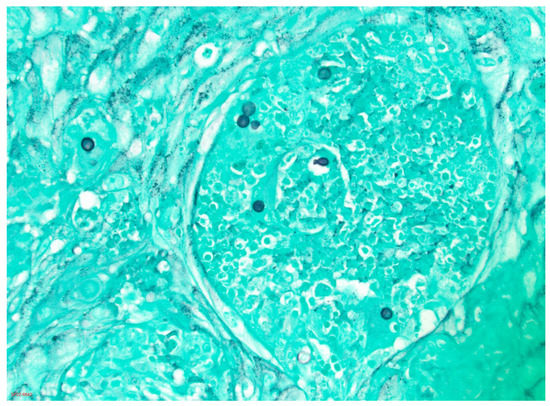

4.2. Histopathology and Cytology